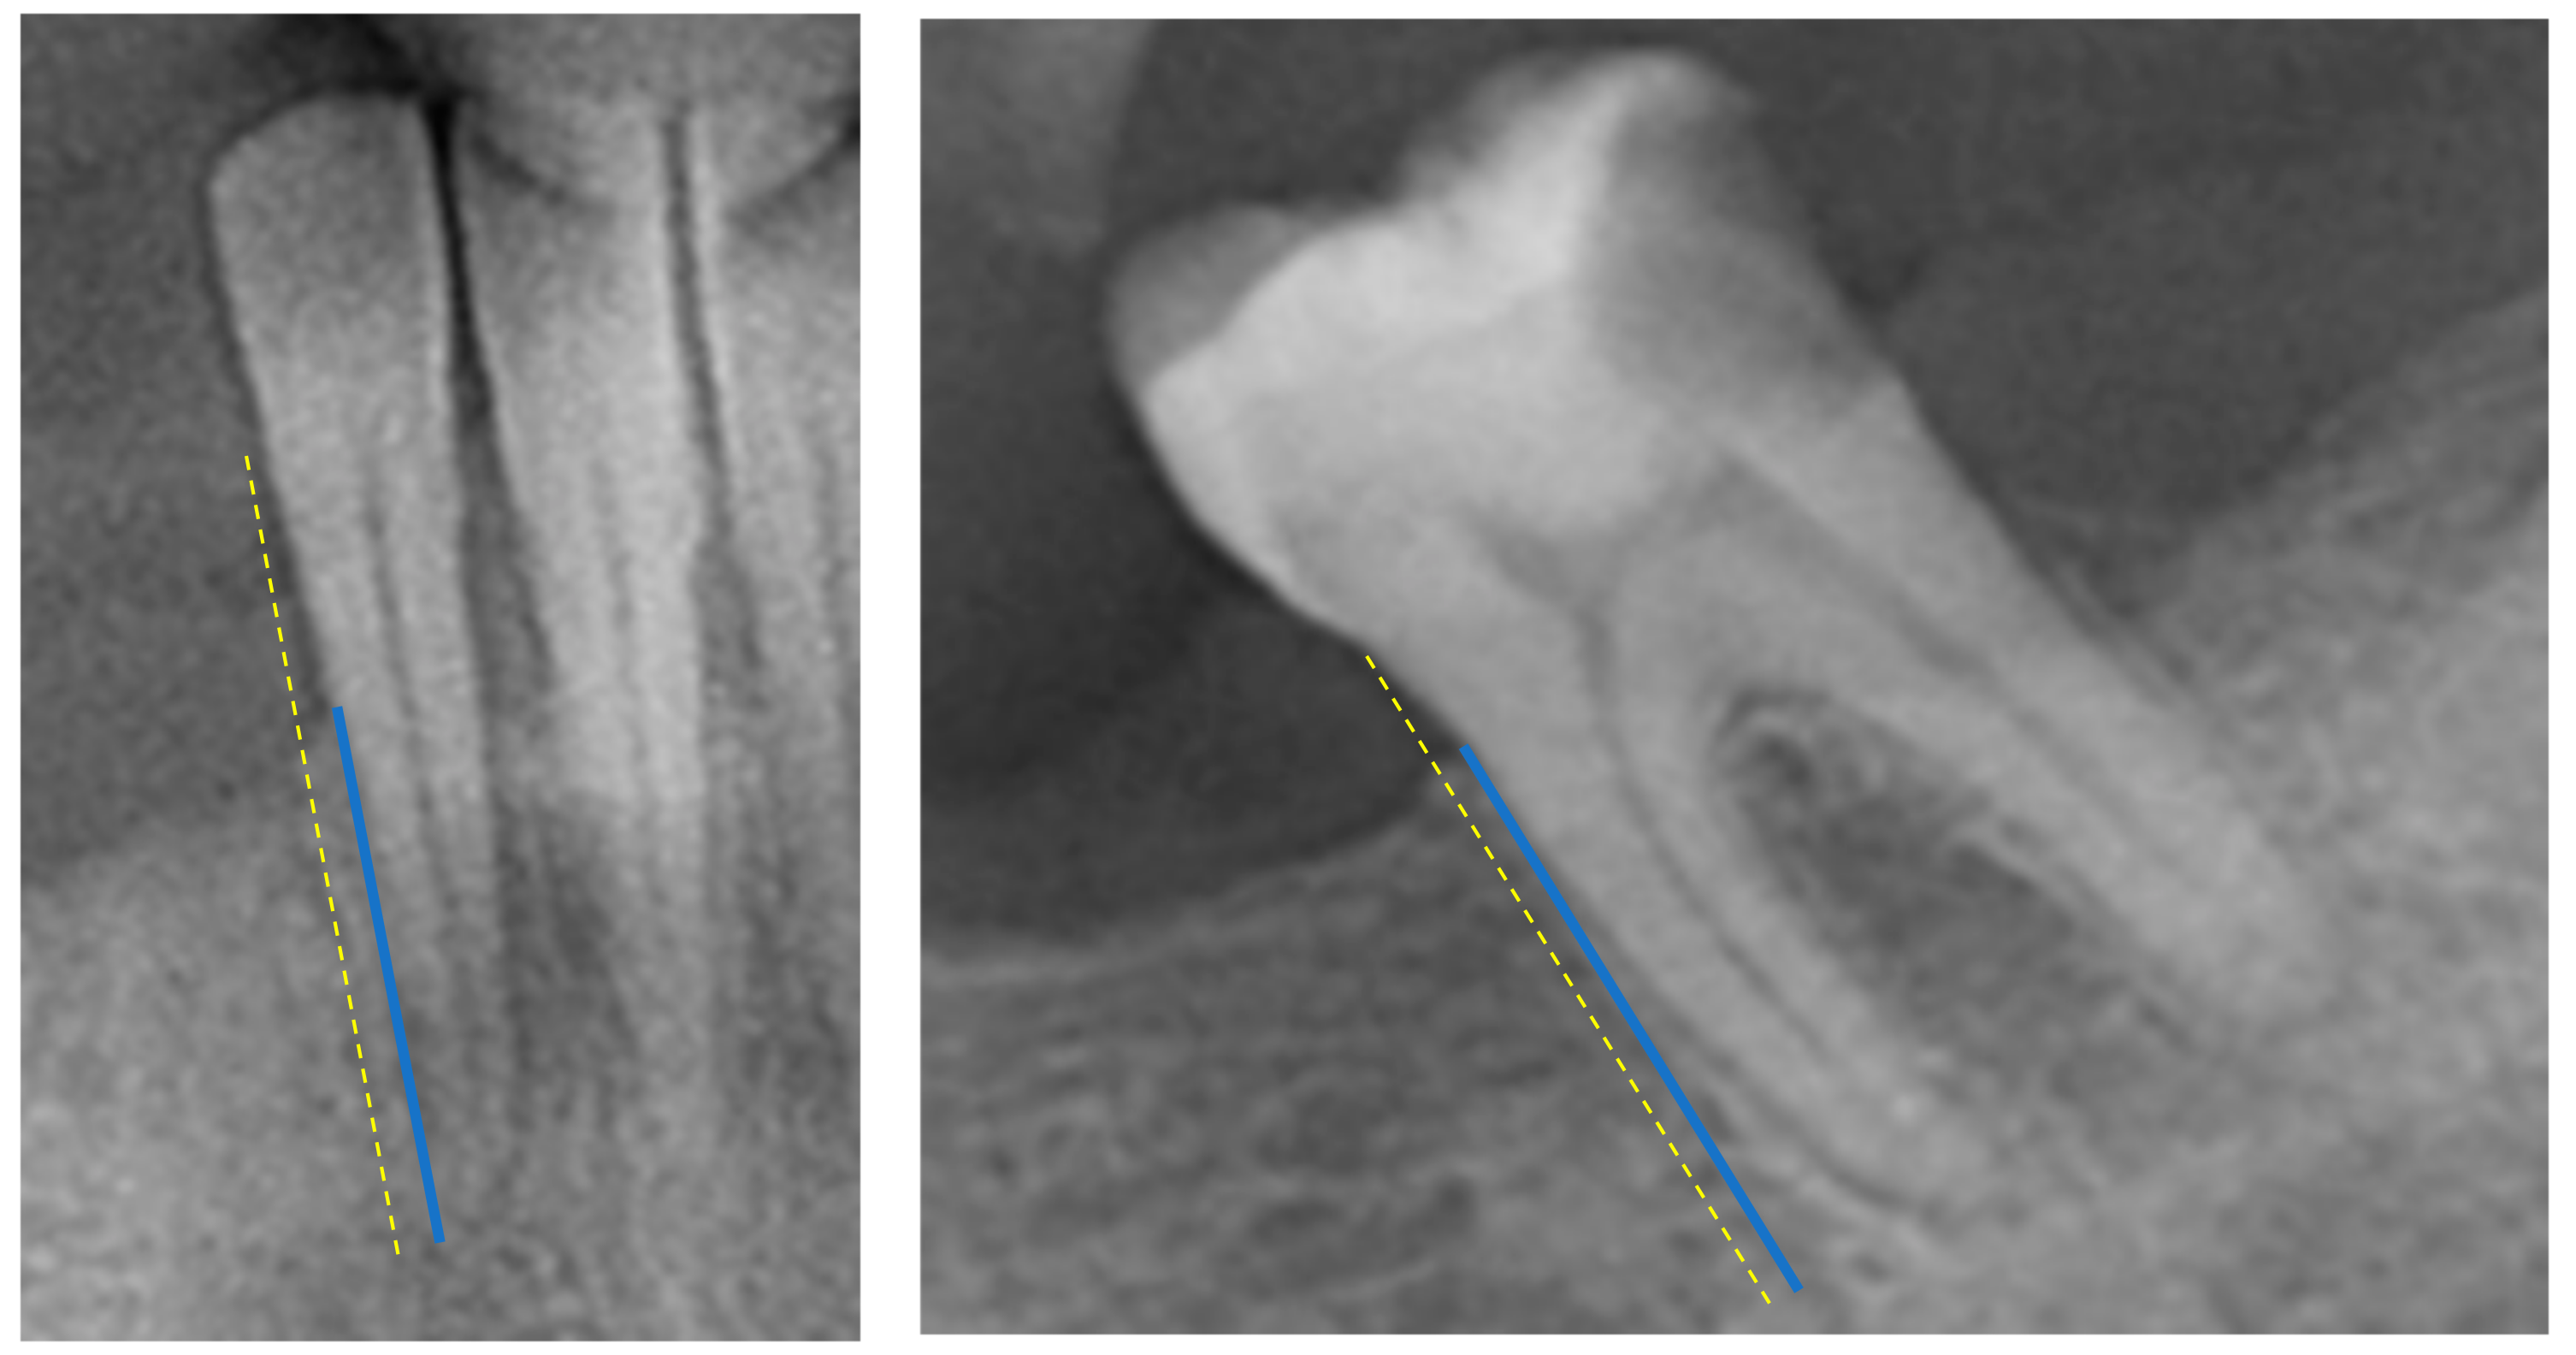

• Periodontal Bone Loss (PBL)—the radiographic PBL was assessed by measuring the total root length (distance from the tooth’s apex to the cementoenamel junction) and the total bone height (distance from the tooth’s apex to the marginal alveolar bone) in each tooth, as described in previous research [14] (Figure 1). Measurements were performed with a high-resolution computer monitor in a darkened room. For these measurements, the arithmetic mean was then calculated and used as a measure of proportion (%). Based on the PBL, as a percentage, patients were then divided into different groups: Healthy Periodontium (if PBL ≥ 80%), Mild-to-Moderate Periodontitis (if PBL ranged between 79 and 66%), and Severe Periodontitis (if PBL < 66%) [15]. These measurements were conducted using ImageJ software (Image Tool 3.0 software program, Department of Dental Diagnostics Science, University of Texas Health Science Center, San Antonio, TX, USA).

Figure 1. Radiograph-based Periodontal Bone Loss (R-PBL) was measured from the marginal alveolar bone to the tooth apex (blue line) and from the cementoenamel junction to the tooth apex (yellow dotted line).